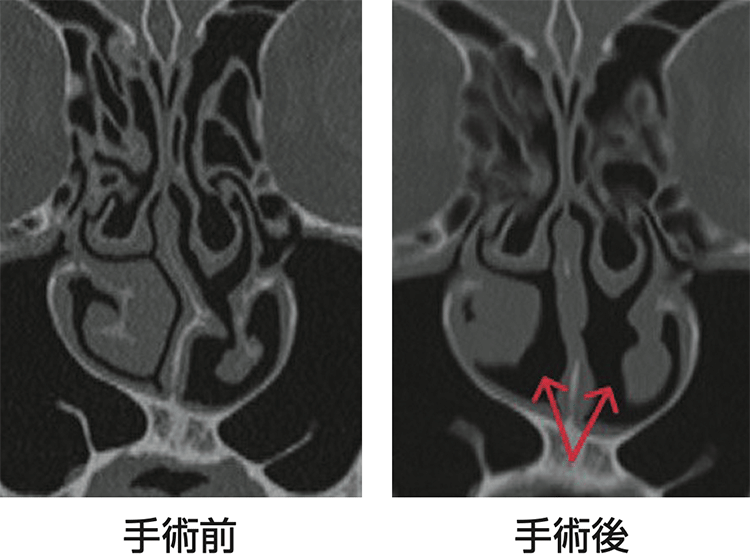

手術治療は、鼻中隔弯曲症(びちゅうかくわんきょくしょう)を伴う患者さん、繰り返し生じたアレルギー反応で非可逆性の粘膜肥厚(※2)を生じた患者さんで検討します。内視鏡で行う手術ですが、基本的には入院が必要な全身麻酔手術になります(図2)。日帰りの手術であれば、レーザーなどで粘膜を焼灼(しょうしゃく)してアレルゲンへの反応性を低下させる下鼻甲介粘膜焼灼術(かびこうかいねんまくしょうしゃくじゅつ)があります。患者さんの状態や希望に合わせて選択していきます。

手術治療は、コロナ禍の2022年の1年間で、鼻中隔矯正術は93件、鼻粘膜の減量手術は126件、鼻汁の分泌を減らす後鼻神経切断術は4件行っています。